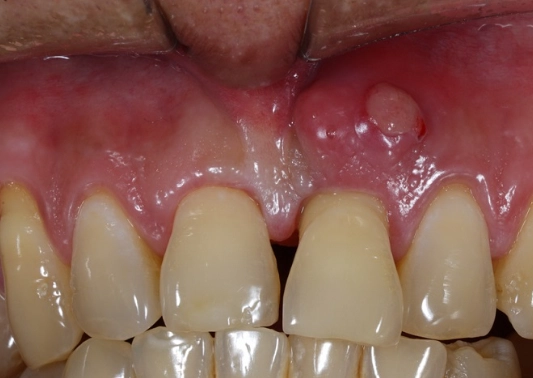

- Swelling in the face, cheek, or jaw: This can range from a slight puffiness to a significant, hard swelling that distorts your face.

- That "pimple on the gum" (fistula): It might drain a bad-tasting, salty fluid, providing temporary relief.